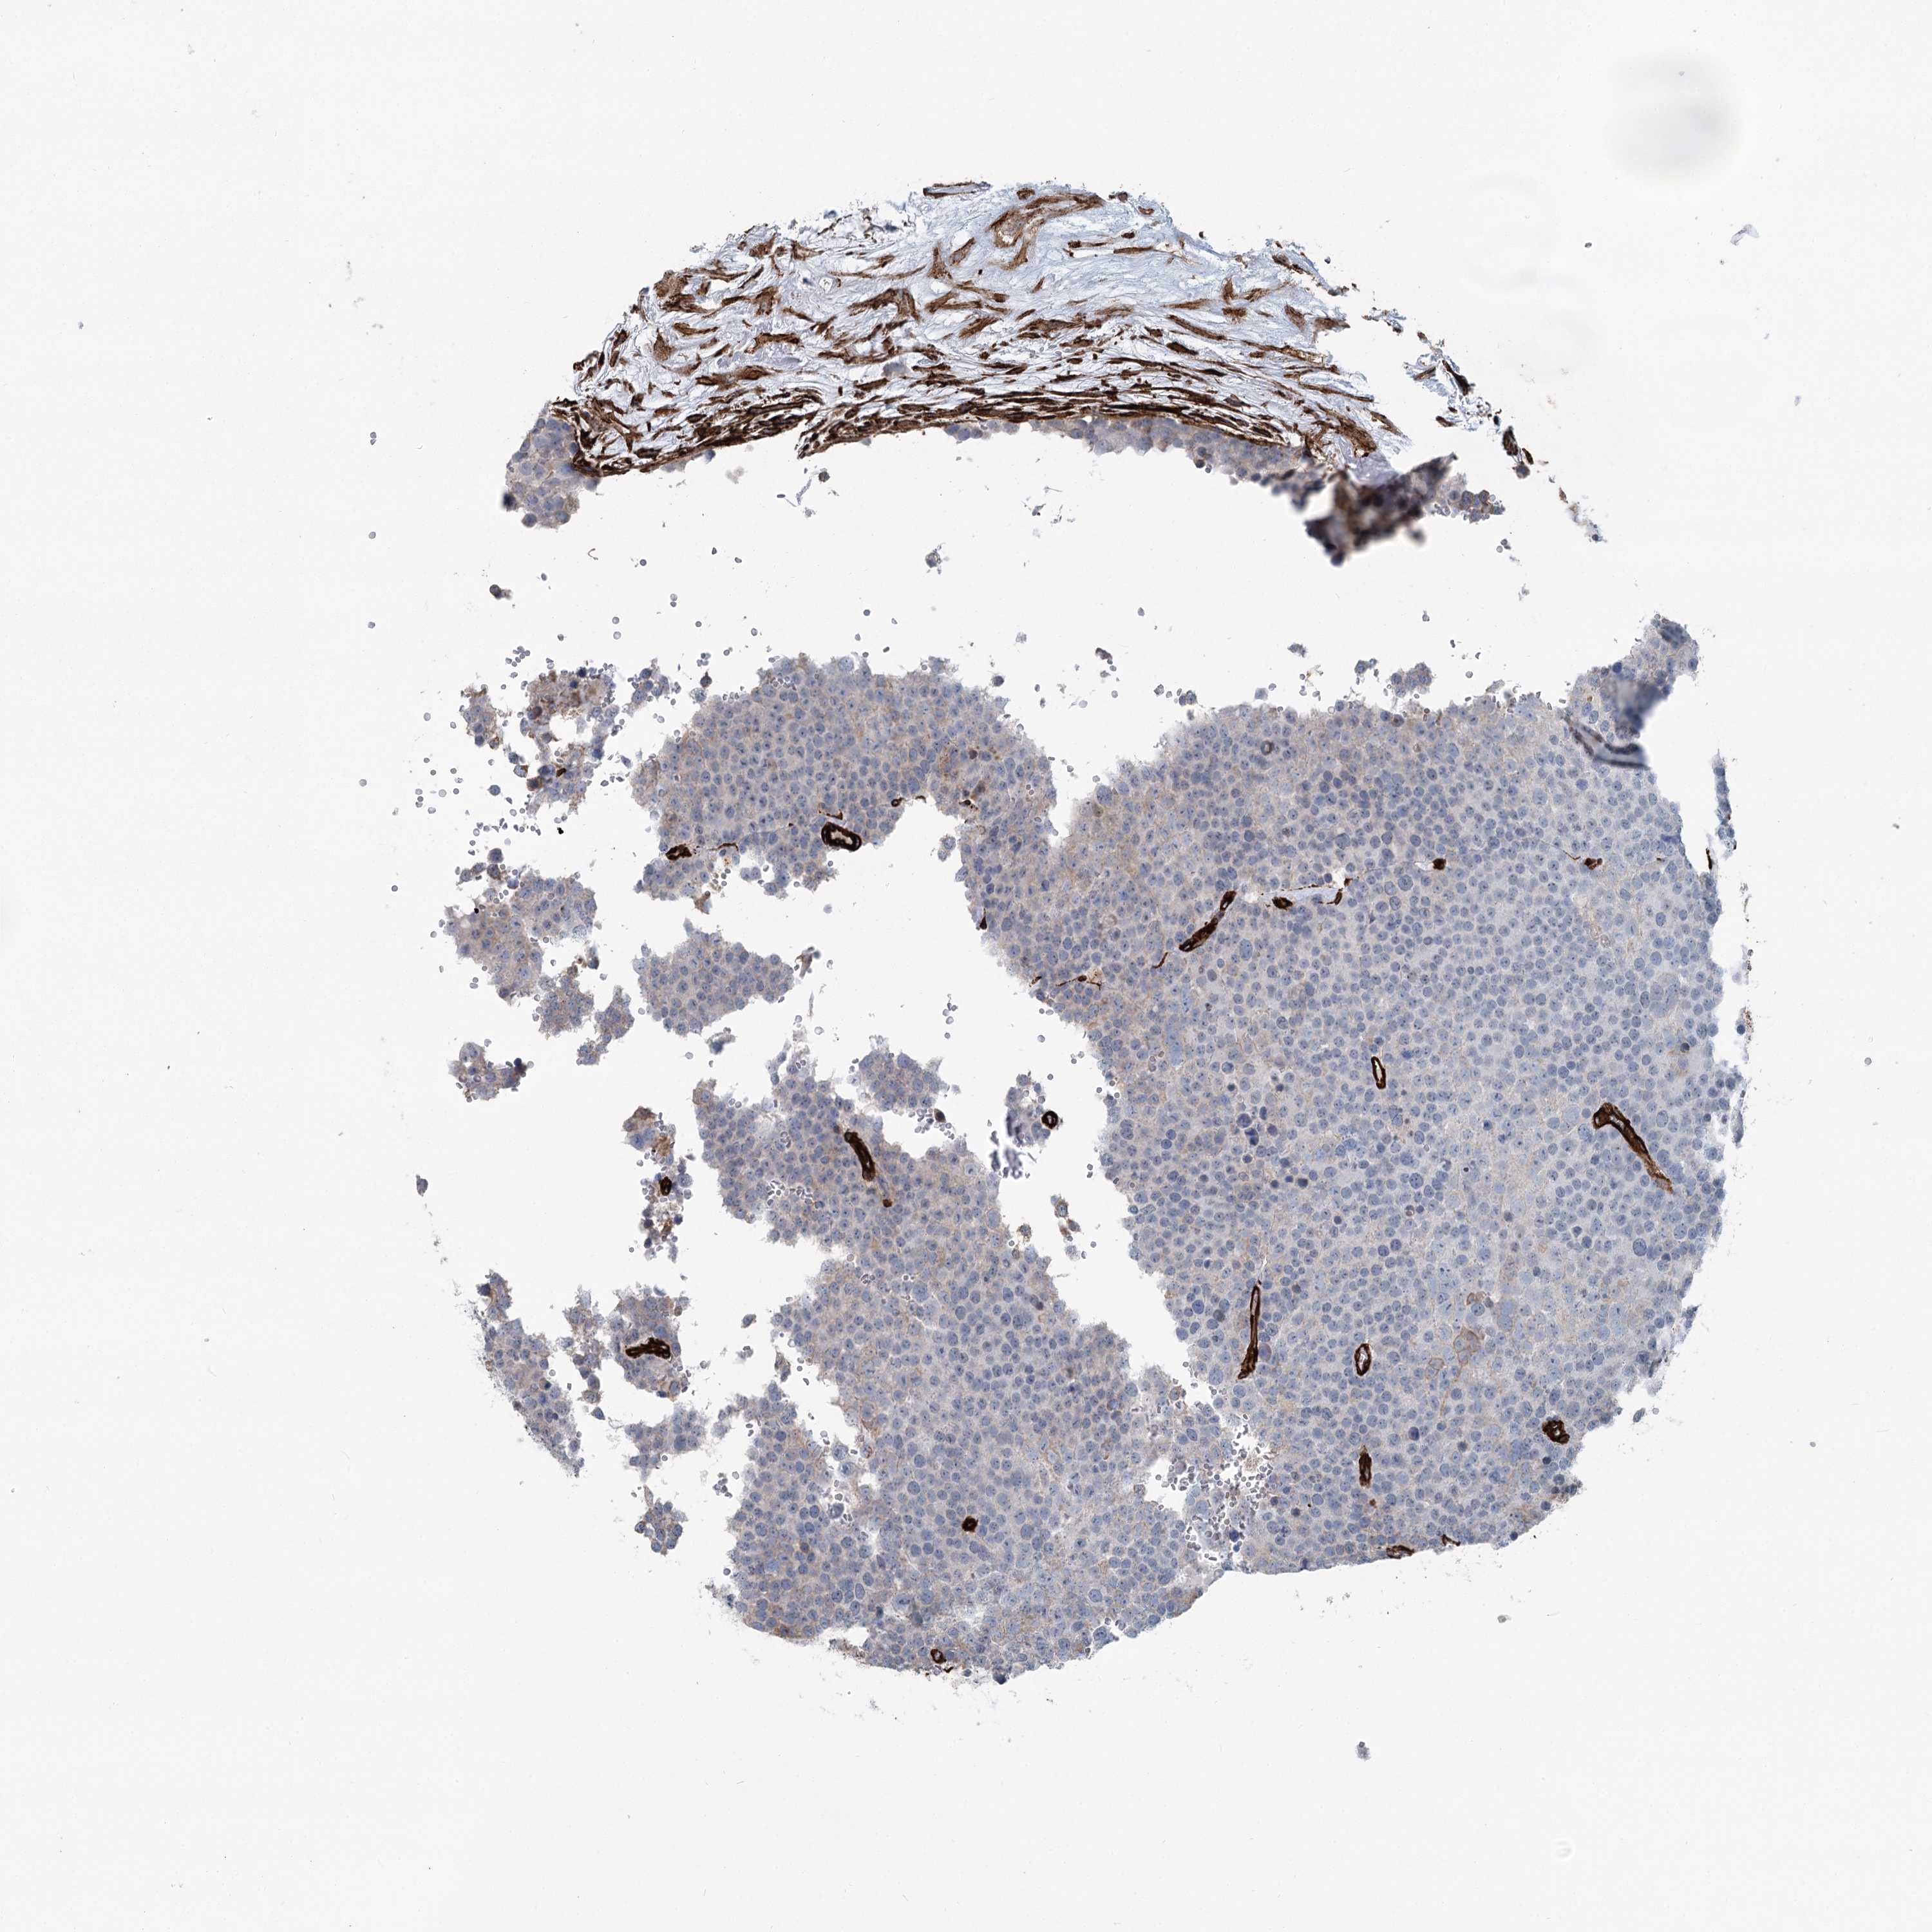

TESTIS CANCER - Protein expressioni

A mouse-over function shows sample information and annotation data. Click on an image to view it in a full screen mode. Samples can be filtered based on level of antibody staining by selecting one or several of the following categories: high, medium, low and not detected. The assay and annotation is described here.

Note that samples used for immunohistochemistry by the Human Protein Atlas do not correspond to samples in the TCGA dataset.

Antibody stainingi

Antibody staining in the annotated cell types in the current human tissue is reported as not detected, low, medium, or high, based on conventional immunohistochemistry profiling in selected tissues. This score is based on the combination of the staining intensity and fraction of stained cells.

Each image is clickable and will lead to virtual microscopy that enables deeper exploration of all samples and also displays staining intensity scores, fraction scores and subcellular localization as well as patient and tissue information for each sample.

Antibody HPA038143

Antibody HPA038144

Carcinoma, Embryonal, NOS

Seminoma, NOS

Urothelial carcinoma, High grade